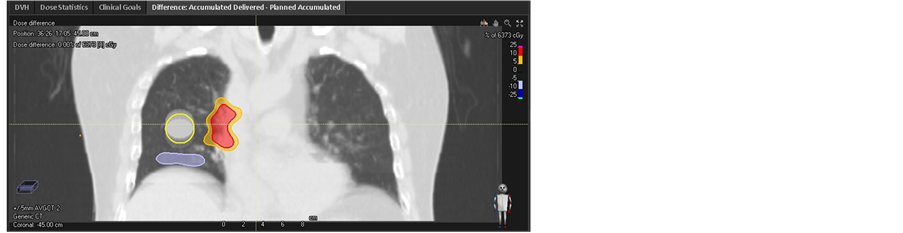

Each phase dose distribution was acquired using the plan had been implemented on the designing CT set respectively. Figure 3 demonstrates the dose volume histogram (DVH) of GTV for each phase and initial plan. In the case of MIP CT and CTavg_only based planning, the dispersion of GTV’s DVH is significantly larger comparing to the CTavg_tumor and CTavg_muscle based planning strategies which indicates lower dose delivered to target overall treatment due to using the inappropriate CT average image sets. The minimum of D98 for GTV reach 55.14 Gy in phase 5 mm and 47.51 Gy in phase 5 mm in the plan based MIP CT with initial GTV D98 = 60.09 Gy and CTavg_ only with initial GTV D98 = 60.10 Gy respectively. The dose difference on GTV was shown in Figure 4. While the worst case of D98 for GTV in the plan based CTavg_ tumor with initial GTV D98 = 60.07 Gy and CTavg_muscle with initial GTV D98 = 60.4 Gy are 58.29 Gy and 59.31 Gy respectively. CTavg_muscle shows slightly better coverage in the worst-case breathing phase image set. Table 1 lists the detail result.

The accumulative dose was calculated by sum up total phase dose distribution using the corresponding DVF. The dose difference and DVH between accumulative dose and planned dose on target were shown in Figure 5. In fact, the D98 of cumulative dose for GTV based CTavg_only and MIP CT are 53.48 Gy and 57.68 Gy, the corresponding discrepancy compared to planned dose reach to −11% and −4% respectively. While the D98 of cumulative dose for GTV based CTavg_muscle and CTavg_tumor are acquired as 60.19 Gy with discrepancy 0% and 59.73 Gy with discrepancy −1%, which is close to the initial plan dose. The dose discrepancy on GTV between cumulative dose and initial dose are larger for MIP CT and CTavg_only sensitivity of proton range and motion of the tumor uncertainties. While the corresponding discrepancy are relatively small for CTavg_muscle and CTavg_tumor, which is the reason that the proton plan was often implemented on CTavg_muscle or CTavg_tumor in most of the proton clinic.

Figure 5. Dose difference between accumulation and initial plan based on (a1) CTavg_tumor, (b1) CTavg_muscle, (c1) CTavg_only, (d1) MIP, GTV comparison DVH between accumulation and initial plan based on (a2) CTavg_tumor, (b2) CTavg_muscle, (c2) CTavg_only, (d2) MIP CT.